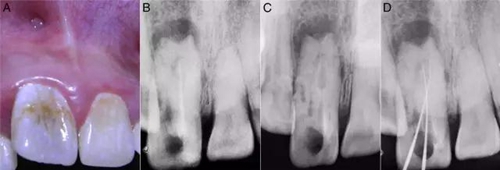

檢查:11曾做過根管治療、叩診(+)。冠修復(fù)脫落,暴露根管口和齲壞的牙體組織,還有近遠(yuǎn)中腭溝深齲延伸至釉牙骨質(zhì)界。11較21尺寸要大并向唇側(cè)傾斜、冠1/3突出,中間部分凹陷。唇前庭有局部的棕色斑點(diǎn)和竇道開口(圖1A)。牙髓電活力測試和冷熱診均呈陰性反應(yīng)。

X線檢查:11暗示有牙內(nèi)陷的發(fā)育畸形,冠根呈桶狀。根管復(fù)雜但只有一個根尖孔,先前的根管充填并不徹底。還有中等大小的根尖周病變(圖1B)。

圖1:A:11外部形態(tài);B:11之前的根管治療;C:牙膠去除后,牙內(nèi)陷的形狀、可以看出復(fù)雜根管和盲袋;D:DM傾斜走形和MI在根尖區(qū)重疊。